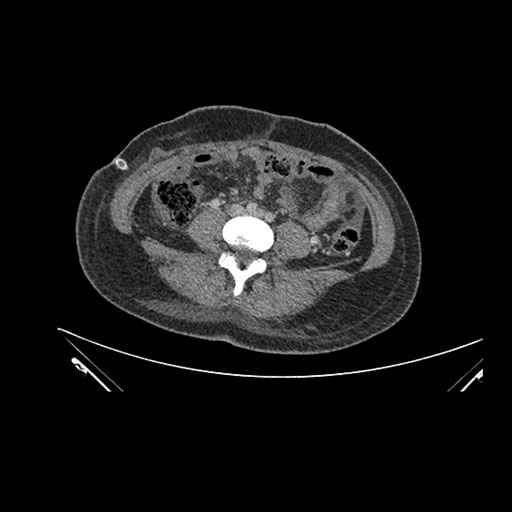

Imaging Analysis

Look through the patient's CT scan to identify any areas of concern for the necessary procedure.

Based on initial findings, which issue(s) would you be most concerned about?